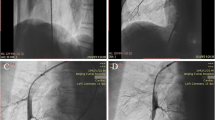

All CTPA images were evaluated by two board-certified radiologists with 11 and 14 years of experience, respectively. Blinding the clinical data was ensured by using a dedicated commercially available diagnostic workstation (Centricity RA 1000, GE Healthcare). The widest short-axis diameter of the main pulmonary artery (dPA) was measured, and the mean of two perpendicular measurements of the ascending aortic diameter (the aortic diameter [dAA]) was calculated using transverse images at the level of the PA bifurcation (Fig. 1a, b); the dPA/dAA ratio was calculated [20, 21]. The widest long-axis diameter of the right atrium (dRA) and the widest short-axis diameters of the right (dRV) and left ventricles (dLV) were also measured on the transverse images (Fig. 1c, d); the dPA/dRA ratio and dRV/dLV ratio were calculated [21]. Diameter of the right ventricular free wall thickness (dRVW) was also measured (Fig. 1c, d) according to previous literature [22]. The measurements of the blood vessel, atrium, and ventricle diameters were performed using the outer limits of the filled contrast medium.

Vascular and cardiac chamber diameter measurements on computed tomography pulmonary angiography images. The widest short-axis diameter of the main pulmonary artery (dPA) is measured, and the mean of two perpendicular measurements of the ascending aortic diameter to represent the aortic diameter (dAA) is calculated using transverse images at the level of the PA bifurcation (orange, blue, and green lines in Fig. 1a, b, respectively). The dPA/dAA ratio is calculated. The widest long-axis diameter of the right atrium (dRA), the widest short-axis diameters of the right and left ventricles (dRV, dLV), and the short-axis diameters of right ventricular free wall thickness (dRVW) are also measured on transverse images (orange, blue, green, and yellow lines in Figs. 1c, d, respectively). The dPA/dRA ratio and dRV/dLV ratio are calculated.